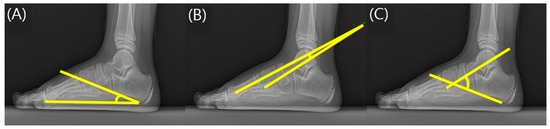

Foot radiographs were taken to evaluate the structural and anatomical deformities of the feet in flatfoot patients. To image the flatfoot, patients were asked to take off shoes and maintain a standing position in a weight-bearing position, and X-ray imaging of the foot was performed in the anteroposterior (AP) and lateral view. A previous study by Harris reported that there was a clinical correlation between calcaneal pitch angle (CPA), talometatarsal angle (TMA), and talocalcaneal angle (TCA) in children with flexible flatfoot [18]. The rehabilitation doctor with more than 3 years of experience measured the CPA, TMA, and TCA for each foot in the lateral view using PACS computer software according to the method mentioned by Sinha et al. [19] (Figure 3). The CPA measured the angle of the foot’s bottom line extending from the lower part of the calcaneocuboid joint to the lower boundary of the calcaneus and the line extending from the lower side of the medial calcaneus to the inferior boundary in the lateral view of the foot radiograph. The TMA was measured as the angle formed by the line that bisects the line tangent to the upper and lower edges of the talus at right angles and the line extending from the center of the metatarsal head. The TCA was measured as the angle between the line connecting the bottom boundary of the calcaneus and the line connecting the two center lines of the talus.

Figure 3.

Measurement of radiographic parameters. (A) Calcaneal pitch angle; (B) Talometatarsal angle; (C) Talocalcaneal angle.